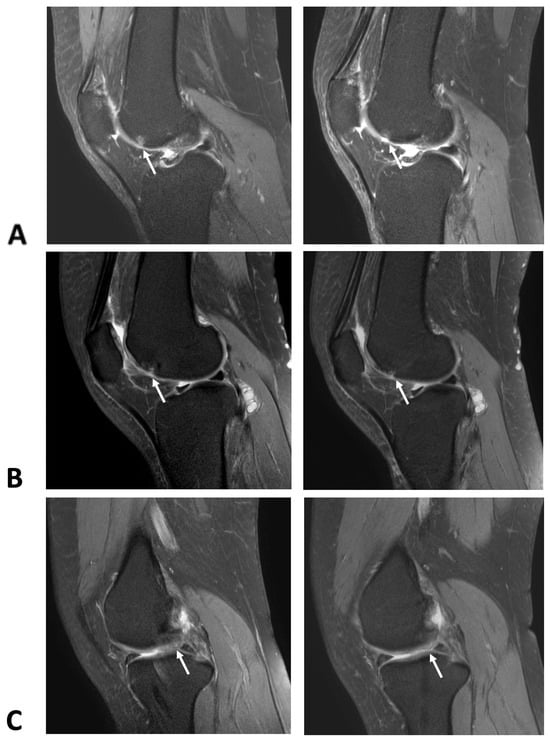

2.1. Cartilage Regeneration and Structural Changes

2.2. Reduction in Synovial Thickness